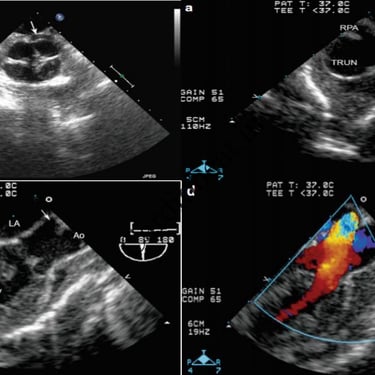

Truncus Arteriosus